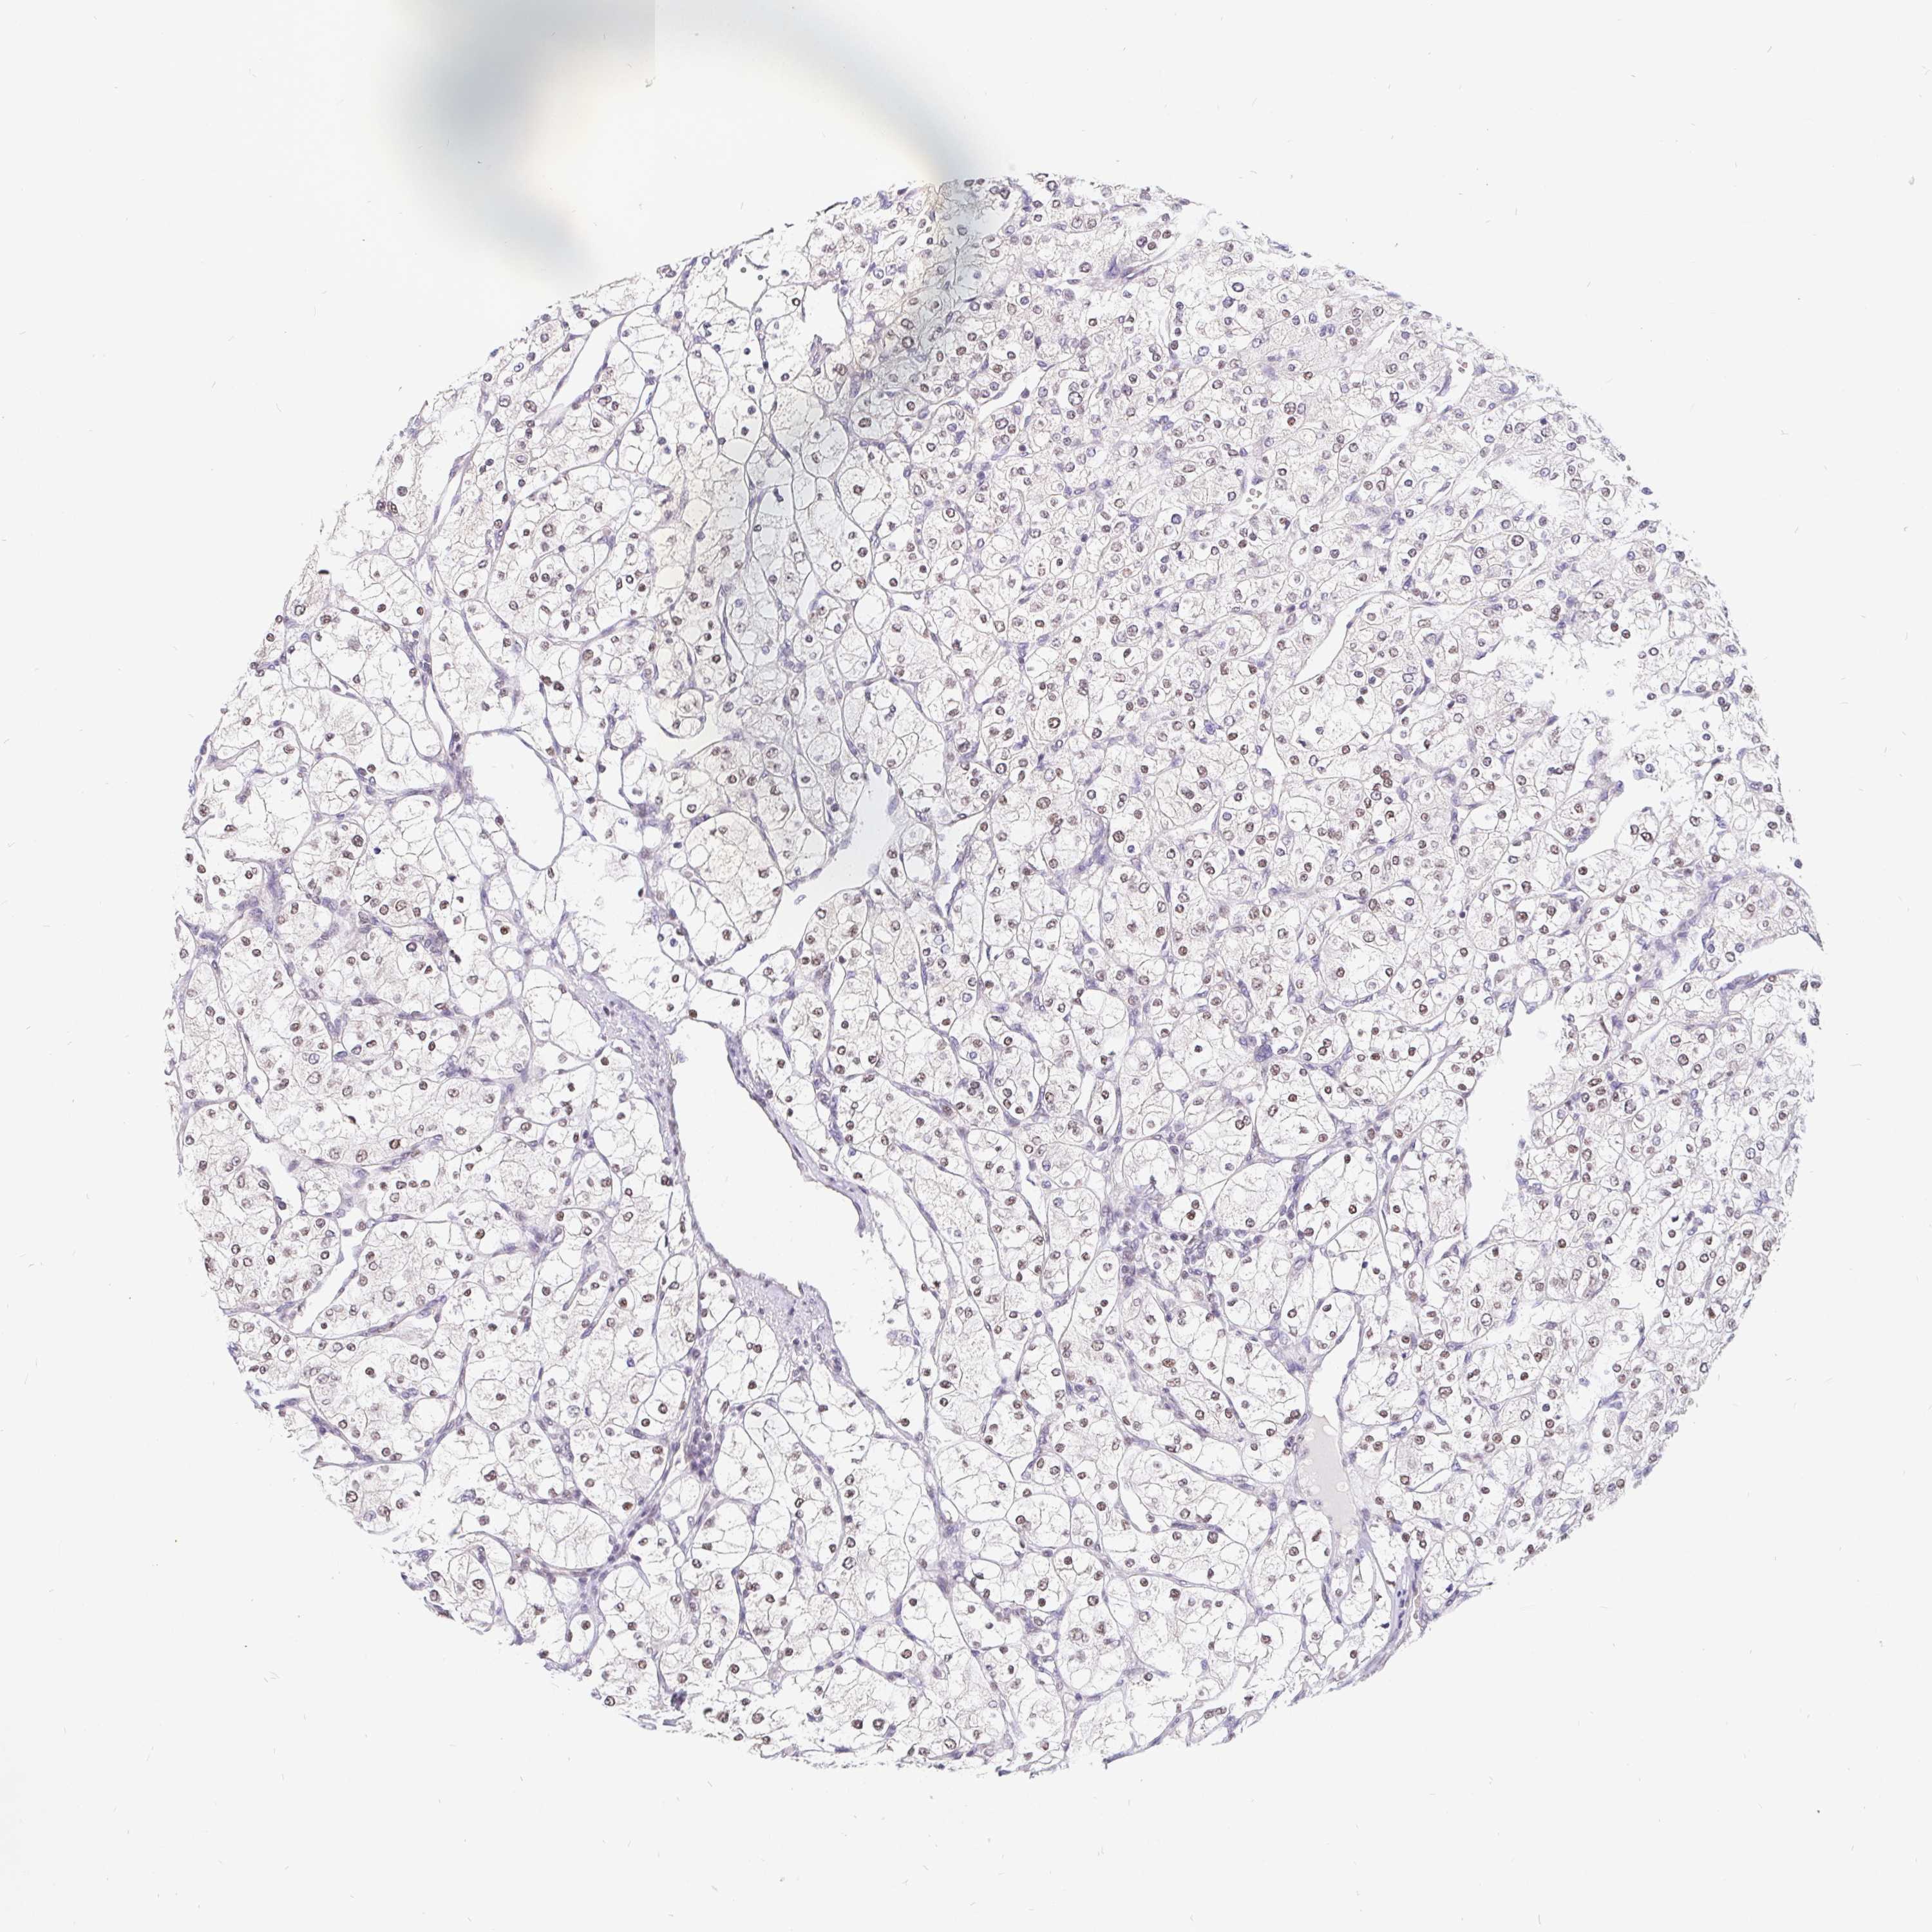

KIDNEY RENAL PAPILLARY CELL CARCINOMA (TCGA) - Interactive survival scatter ploti

The Survival Scatter plot shows the clinical status (i.e. dead or alive) for all individuals in the patient cohort, based on the same data that underlies the corresponding Kaplan-Meier plots. Patients that are alive at last time for follow-up are shown in blue and patients who have died during the study are shown in red.

The x-axis shows the expression levels (FPKM) of the investigated gene in the tumor tissue at the time of diagnosis. The y-axis shows the follow-up time after diagnosis (years). Both axes are complimented with kernel density curves demonstrating the data density over the axes. The top density plot shows the expression levels (FPKM) distribution among dead (red) and alive patients (blue). The right density plot shows the data density of the survived years of dead patients with high and low expression levels respectively, stratified using the cutoff indicated by the vertical dashed line through the Survival Scatter plot. This cutoff is automatically defined based on the FPKM cutoff that minimizes the p-score. The cutoff can be changed by dragging the vertical line or by entering a cutoff value in the square labeled "Current cut-off".

Under the Survival Scatter plot the p-score landscape (black curve; left axis) is shown together with dead median separation (red curve; right axis). Dead median separation is the difference in median mRNA expression between patients who have died with high and low expression, respectively. It is calculated as follows: median FPKM expression of dead patients with high expression - median FPKM expression of dead patients with low expression. This is intended to aid the user in visually exploring custom cutoffs and the associated p-scores and dead median separation.

Individual patient data is displayed and can be filtered by clicking on one or more of the category buttons on the top of the page. Categories describing expression level and patient information include: high, low, alive, dead, female, male and tumor stages. The scale of the x-axis can be toggled between linear and log-scale by clicking on the "x log" button. Mouse-over function shows TCGA ID, patient information and mRNA expression (FPKM) for each patient.

& Survival analysisi

Kaplan-Meier plots summarize results from analysis of correlation between mRNA expression level and patient survival. Patients were divided based on level of expression into one of the two groups "low" (under cut off) or "high" (over cut off). X-axis shows time for survival (years) and y-axis shows the probability of survival, where 1.0 corresponds to 100 percent.

POU2F1 is not prognostic in Kidney Renal Papillary Cell Carcinoma (TCGA)

Best expression cut offi

Based on the FPKM value of each gene, patients were classified into two groups and association between prognosis (survival) and gene expression (FPKM) was examined. The best expression cut-off refers the FPKM value that yields maximal difference with regard to survival between the two groups at the lowest log-rank P-value. Best expression cut-off was selected based on survival analysis .

When clicking on this number, the vertical dashed line indicating cut-off, the interactive survival plot, and the Kaplan-Meier curve will be adjusted to show results based on the best expression cut-off.

: 3.9